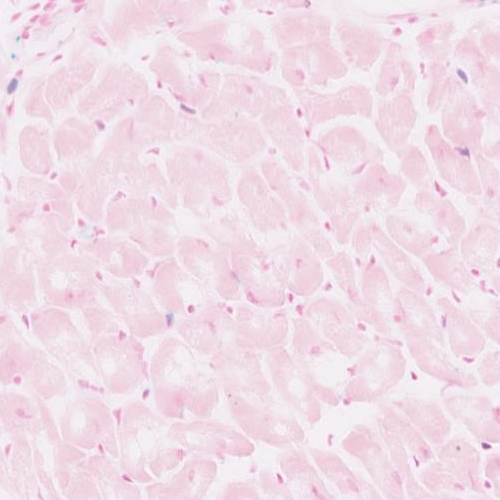

Fig. Plxnd1 Adult heart

J:260776

Full Image

Fig. Plxnd1 E15.5 CardiacMuscle_atria

Fig. Plxnd1 E15.5 CardiacMuscle_ventricular

Fig. Plxnd1 E15.5 upperarm_musc&mesenchyme